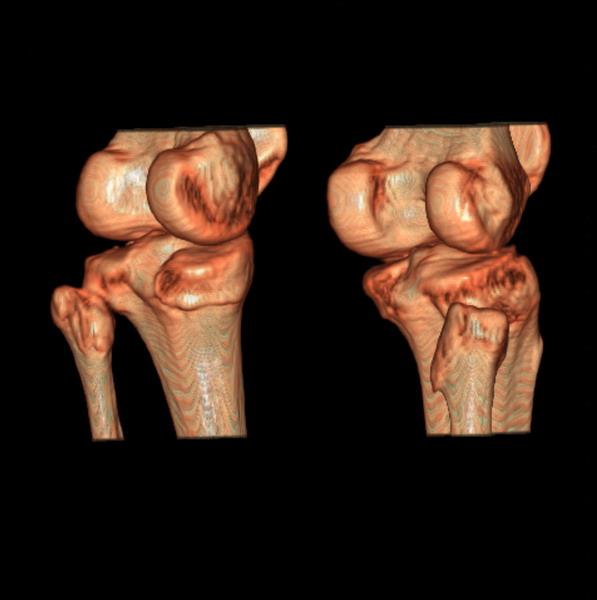

标题: CT21917:右腓骨小头是否骨软骨瘤? [打印本页]

标题: CT21917:右腓骨小头是否骨软骨瘤?

女、43.

不是骨软骨瘤,“牵拽征”,正常变异。有平片吗?

正常变异,“牵拽征”,比目鱼肌牵拽.